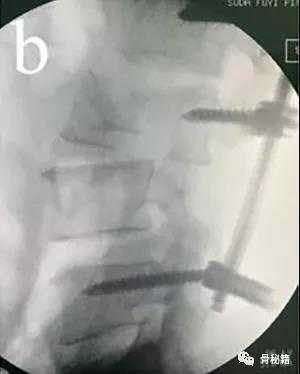

先植入能植入的椎弓根螺钉, 深度过椎弓根即可

先进行短阶段的撑开,撑开之后暴露关键的前移的椎体再植入椎弓根螺钉进行二次撑开

要点:进行初次撑开之后,取下一侧的棒,植入关键椎体的椎弓根螺钉再换另外一侧,同法。

撑开时,可先用直棒,最后复位好了后再进行棒的塑性恢复腰椎前凸来达到较好的稳定

最后添加横联和植骨融合来增加稳定性